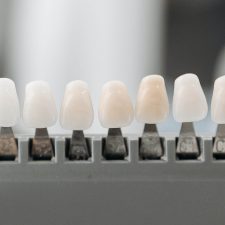

Clínica odontológica, especialistas en estética dental.

Excelente cuidado dental